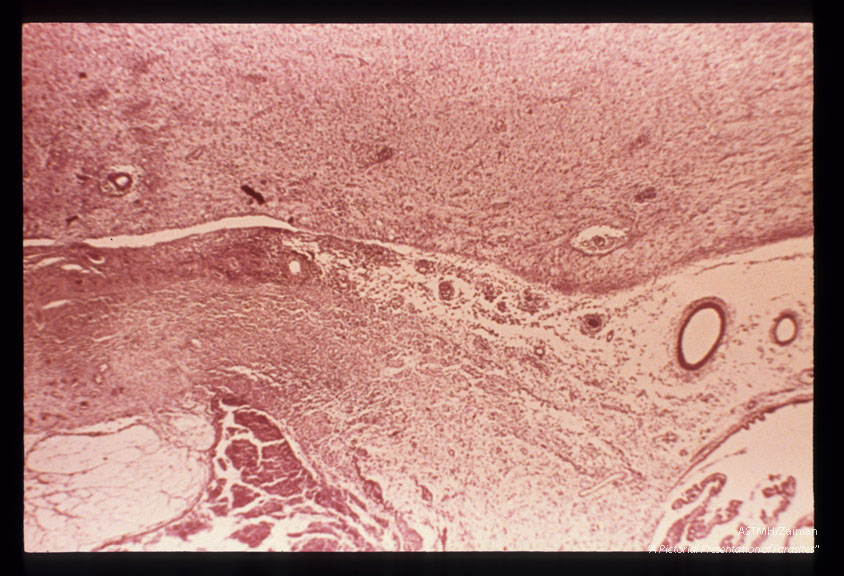

Toxoplasmic encephalitis showing transition of ependymal ulceration to full-blown periventricular necrosis.

Toxoplasma gondii

Description: Toxoplasmic encephalitis showing transition of ependymal ulceration to full-blown periventricular necrosis.